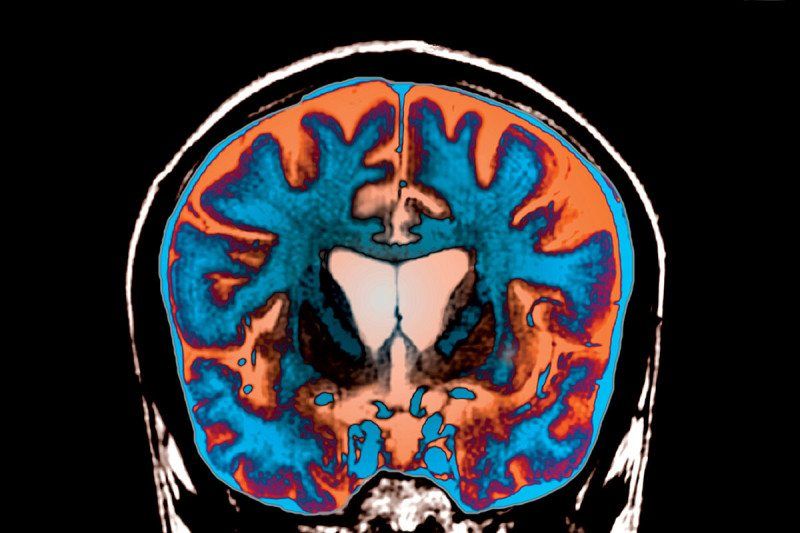

Мозок кожної людини виявився анатомічно унікальним / NewScientist

Генетичні чинники і життєвий досвід впливають на анатомію людського мозку. До такого висновку прийшли команда вчених з Університету Цюріха, які намагалися дати відповідь на питання, чи можуть особливості мозку бути використані для ідентифікації особистості, так само як, наприклад, відбитки пальців.

Мозок музиканта виявився ідеальним для дослідження зв'язку між певними професіями та нейропластичности органу, пише Newsweek . Згодом швейцарські вчені встановили, що навіть короткострокові події, такі як, наприклад, два тижні без рухів лівою рукою, можуть залишити відбиток на ділянці кори, яка відповідає за управління цією кінцівкою.

«Ми підозрюємо, що різні досліди впливають на те, як мозок взаємодіє з генетичним складом. Таким чином, протягом років у кожної людини розвивається абсолютно індивідуальна анатомія мозку », - пояснив доктор нейропсихології Лутц Йенко з Університету Цюріха.

Це відкриття має велике значення, незважаючи на те, що три десятиліття тому вчені були переконані, що мозок у всіх людей майже однаковий. Але завдяки електромагнітної томографії розуміння особливостей функціонування органу значно просунулося вперед за останні роки.